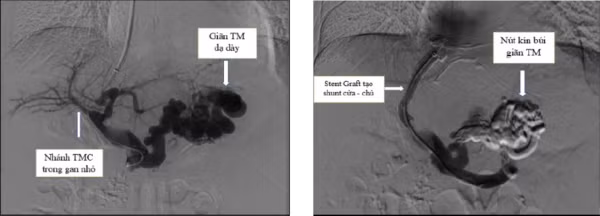

Kỹ thuật TIPS được thực hiện trên một ca bệnh chảy máu do vỡ giãn tĩnh mạch thực quản - dạ dày - Ảnh BVCC

Nguyên lý của kỹ thuật TIPS là việc tạo ra một kết nối trực tiếp giữa tĩnh mạch cửa (portal vein) và tĩnh mạch gan (hepatic vein) bằng cách sử dụng một giá đỡ kim loại (Stent). Từ đó luồng lưu thông máu sẽ chảy trực tiếp từ hệ tĩnh mạch cửa qua stent TIPS sang hệ tĩnh mạch chủ, làm giảm áp lực tĩnh mạch cửa nhằm mục đích cầm máu và giảm tỷ lệ chảy máu tái phát.